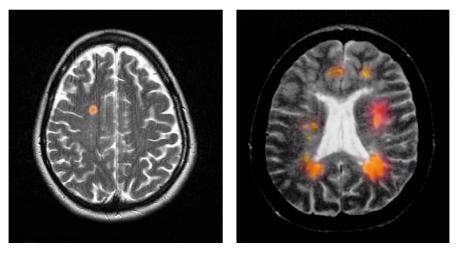

多发性硬化症

多发性硬化症(简称MS)会影响中枢神经系统(脑和脊髓),导致行动不便等问题。 MS随时可能发生,病因是免疫系统攻击神经的髓鞘。在较严重的病例中,神经纤维会严重受损,影响神经信号的传导速度。

从磁振造影扫描可见多发性硬化症造成的脑萎缩程度